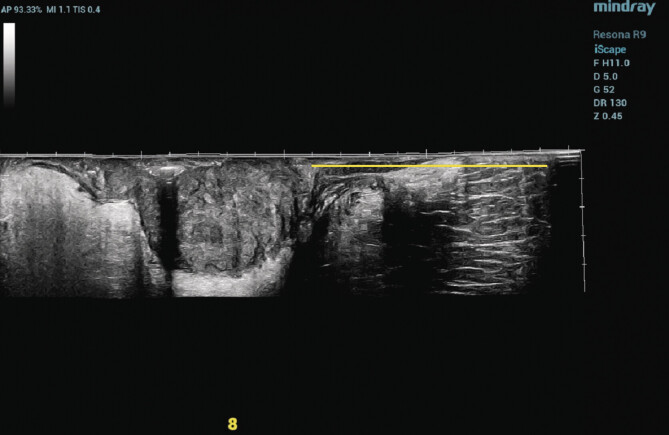

Purpose: This study aimed to measure the precise distance from the lowest boundary of a rectal tumor to the anal verge (DTAV) in patients with rectal cancer.

Materials and methods: A retrospective analysis was performed on clinical data from 70 rectal cancer patients. DTAV measurements were collected using transrectal biplane ultrasound, MRI, and colonoscopy.

Conclusion: Transrectal biplane ultrasound utilizing EFOV imaging technology exhibited both accuracy and reproducibility for measuring DTAV. This approach provided a highly efficient and practical clinical tool for DTAV measurement.

Abstract Image